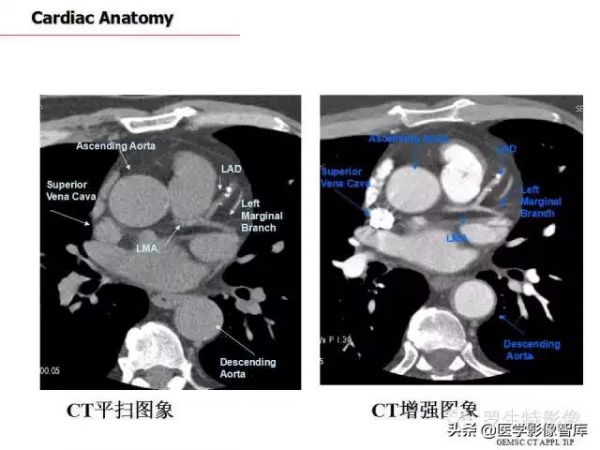

心臟

冠脈

冠狀動脈疾病報告與資料制度(CAD-RADS):

美國心血管CT學會(SCCT)、美國放射學會(ACR)和北美心血管影像學會(NASCI),共同釋出了一份新的報告制度,規範行冠狀動脈CT血管造影(CTA)患者的報告。CAD-RADS規定了0(無狹窄)~5(至少一條動脈完全閉塞)的範圍,根據分類進行進一步成像或處理。修飾符S(支架)、G(移植)和V(易損斑塊)用來更好地描述動脈。

CAD-RADS分類取決於狹窄程度。SCCT建議分類系統為狹窄嚴重程度分級(表1)。表2和表3分別列出穩定性胸痛和急性胸痛的CAD-RADS報告制度分類。

冠脈解剖:

Maximum intensity projection (MIP)

心肌梗死好發部位為左心室前臂心尖部室間隔前2/3。

心肌梗死的好發部位依次為:

①左冠狀動脈前降支所支配的區域,即左室前壁、心尖部、室間隔前2/3部位。

②右冠狀動脈所支配的區域,即左室後壁、室間隔後1/3及右心室。

③左冠狀動脈迴旋支所支配的區域。即:左室側壁。

Course of LAD

Axial CT slide

Left Coronary Artery System

Right Coronary Artery System

Maximum Intensity Projection (MIP)右圓錐支(CB)